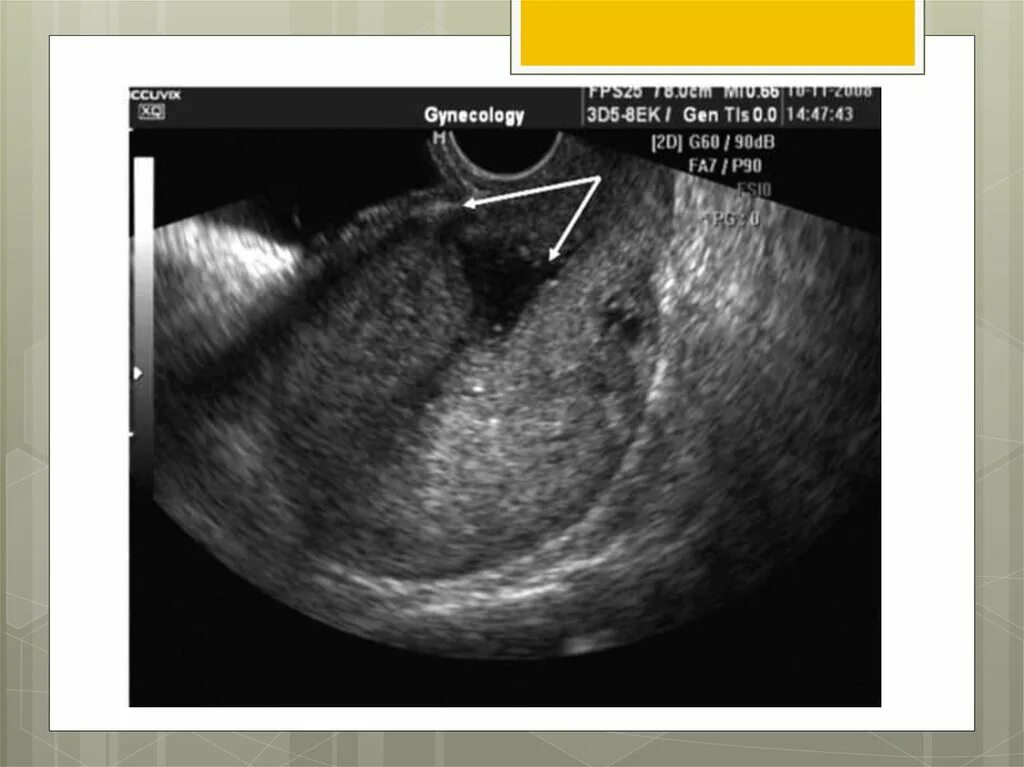

Рубец на матке мкб